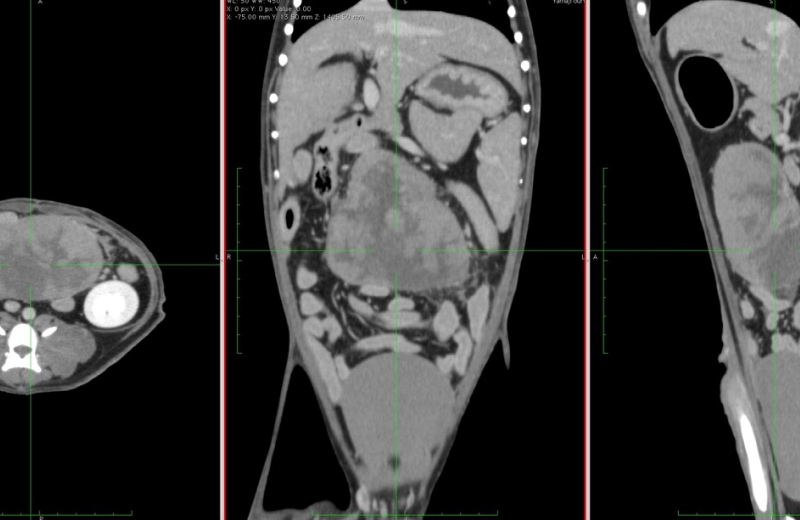

CT スキャン

早く正確な診断のために

CTは、0.5ミリメートルの間隔で断層画像を輪切り画像が作成できるため、ごく小さい病変も描出可能です。

造影剤を使用することにより、腫瘍などの病変部位がわかりやすくなり、腫瘍付近の血管を把握することも可能です。